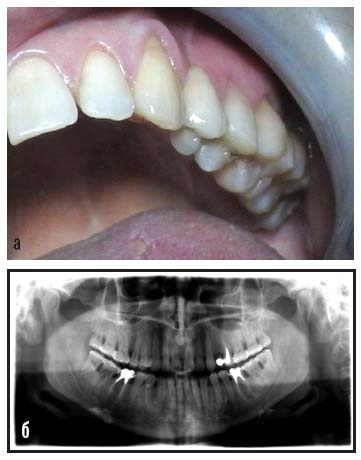

После фиксации ортопедических конструкций, изготовленных лабораторным способом, и укладки АШ эстетика и функциональная целостность зубного ряда восстановлены в полном объеме (рис. 9).

Рис. 9. После замещения дефекта отсутствующего зуба 24 (а); ортопантомограмма после протезирования (б)

Контрольные осмотры в течение года нарушений краевого прилегания АШ не выявили. Через 2 года, по результатам профилактического осмотра, рекомендована незначительная эстетическая коррекция композиционного покрытия (рис. 10).

Рис. 10. Через 2 года после протезирования: а – вид восстановленных эстетическими экваторными коронками зубов 36 и 46, находящихся в составе АШ, выполняющих сагиттальную стабилизацию; б – вид выполненной АШ сагиттальной стабилизации жевательной группы зубов верхнего зубного ряда с объединенным в шину искусственным металлокерамическим зубом 24